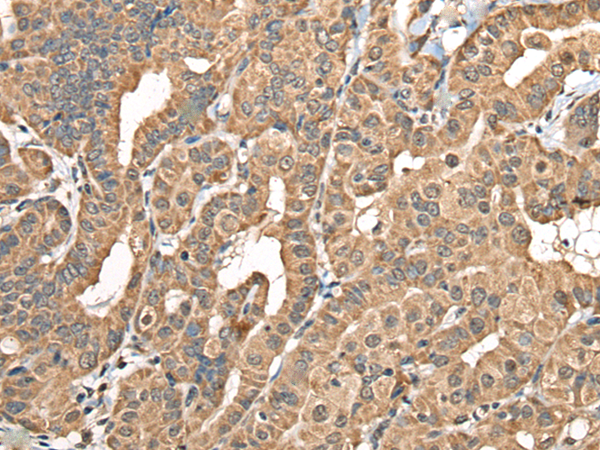

中文名稱: 兔抗NADK2多克隆抗體

英文名稱: Anti-NADK2 rabbit polyclonal antibody

別       名: NAD kinase 2, mitochondrial; DECRD; MNADK; NADKD1; C5orf33

This gene encodes a mitochondrial kinase that catalyzes the phosphorylation of NAD to yield NADP. Mutations in this gene result in 2,4-dienoyl-CoA reductase deficiency. Alternative splicing results in multiple transcript variants.

Applications:

ELISA, WB

Fusion protein of human NADK2

NAD kinase 2, mitochondrial

WB Positive control:

HEPG2, Hela and A549 cell lysates